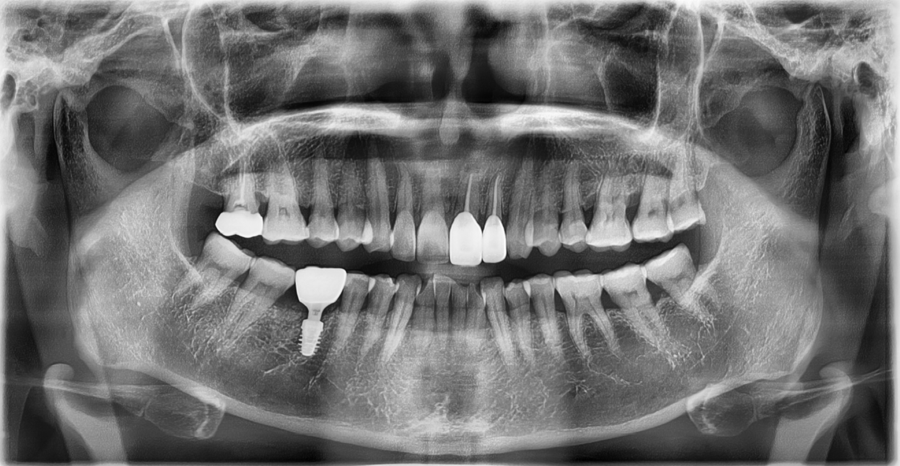

Although the implant fixation itself was relatively stable,

• The direction in which force was transmitted during biting

• The way the prosthesis fit against the surrounding teeth

• The points where repeated stimulation was applied while chewing

worked together and were causing the sensitivity and discomfort.

Previous image

Next image